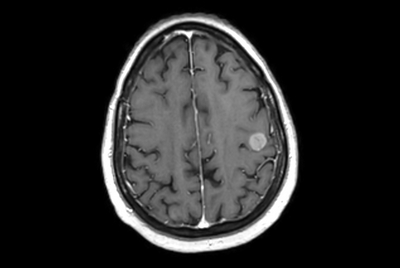

Brain small infarction